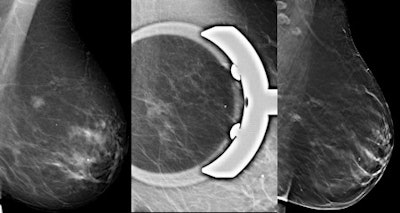

The researchers found that DSCV and DBT both had sensitivities of 100%. However, overall specificity was higher for DBT (100%) than for DSCV (94%). Reader 1 had higher specificity for DSCV (95%) than reader 2 (92%). In addition, reader 1 had two false positives and reader 2 had three false positives for DSCV.

The researchers also found the area under the curve (AUC) was greater for DBT (AUC = 1) than for DSCV (AUC = 0.963). The mean difference between the two techniques, however, was not significantly different.

The mean glandular dose was 4.69 ± 1.7 mGy for the two projections of FFDM added to DSCV and 2.39 ± 0.6 mGy for DBT.

"The results of this study show that DBT is not inferior to digital spot compression in identifying abnormalities judged as suspicious on FFDM," the researchers wrote. "Moreover, DBT had higher specificity than digital spot compression, showing the potential to reduce the number of biopsies on nonmalignant lesions. Moreover, DBT appeared promising with the potential of improving specificity for the less experienced reader."